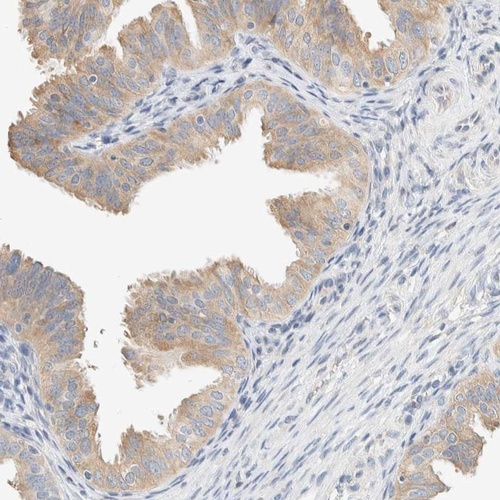

Immunohistochemistry analysis in human fallopian tube and skeletal muscle tissues using Anti-SUMF2 antibody. Corresponding SUMF2 RNA-seq data are presented for the same tissues.